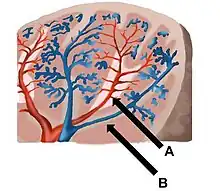

Blood supply

Near the middle of the spleen is a long fissure, the hilum, which is the point of attachment for the gastrosplenic ligament and the point of insertion for the splenic artery and splenic vein. There are other openings present for lymphatic vessels and nerves. In addition to the splenic artery, collateral blood supply is provided by the adjacent short gastric arteries.[14]

Like the thymus, the spleen possesses only efferent lymphatic vessels. The spleen is part of the lymphatic system. Both the short gastric arteries and the splenic artery supply it with blood.[15]

The germinal centers are supplied by arterioles called penicilliary radicles.[16]